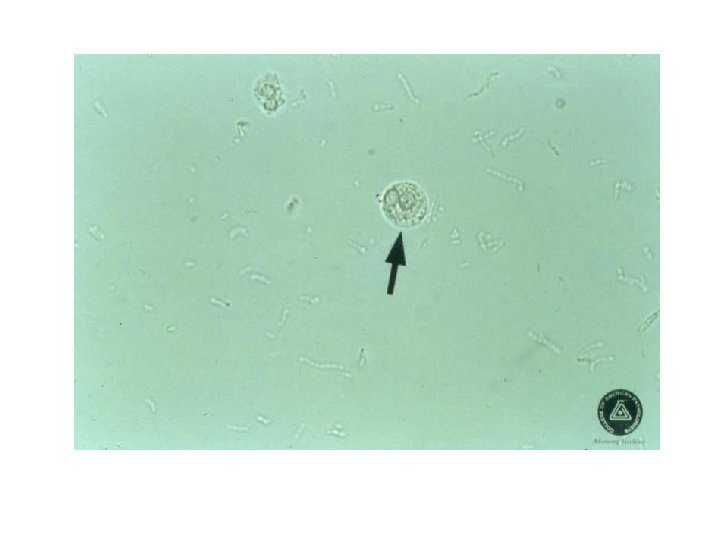

White Blood Cells These appear as round granular 12 -14 μm in diameter Pyuria refers to the presence of abnormal numbers of leukocytes that may appear with infection in either the upper or lower urinary tract or with acute glomerulonephritis. May indicate urinary tract infection UTI if more than 10/HPF

Pyuria